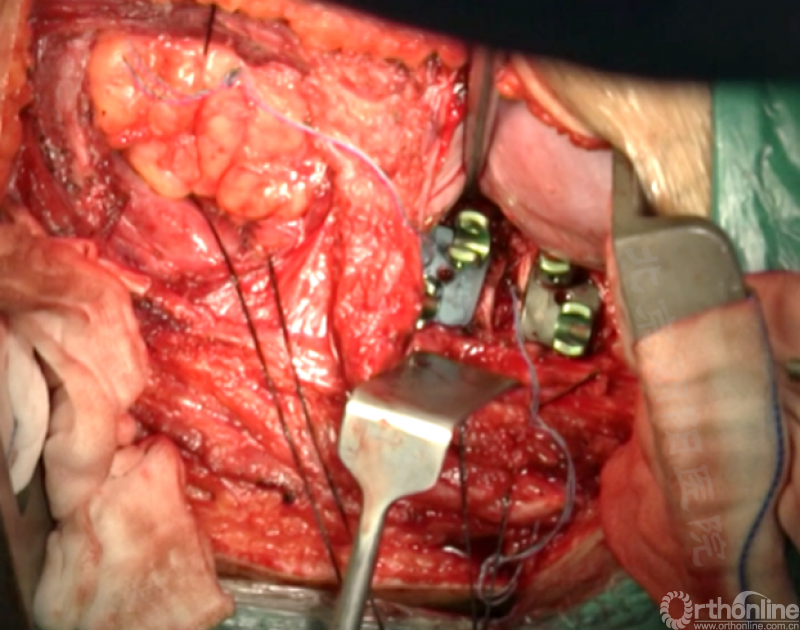

矫正后神经检测未见异常术中唤醒患者下肢活动良好,术中透视矫正效果满意、内固定位置良好。根据手术具体情况放置合适尺寸的横连接加强内固定。

尽量多的闭合胸膜,紧密缝合横膈。

分别缝合第11、12肋骨的骨膜。

留置合适直径的胸腔闭式引流管,根据术中情况选择是否放入腹腔引流。逐层缝合腹壁,逐层缝合皮下组织和皮肤。

患者术前术后大体照及X片对比